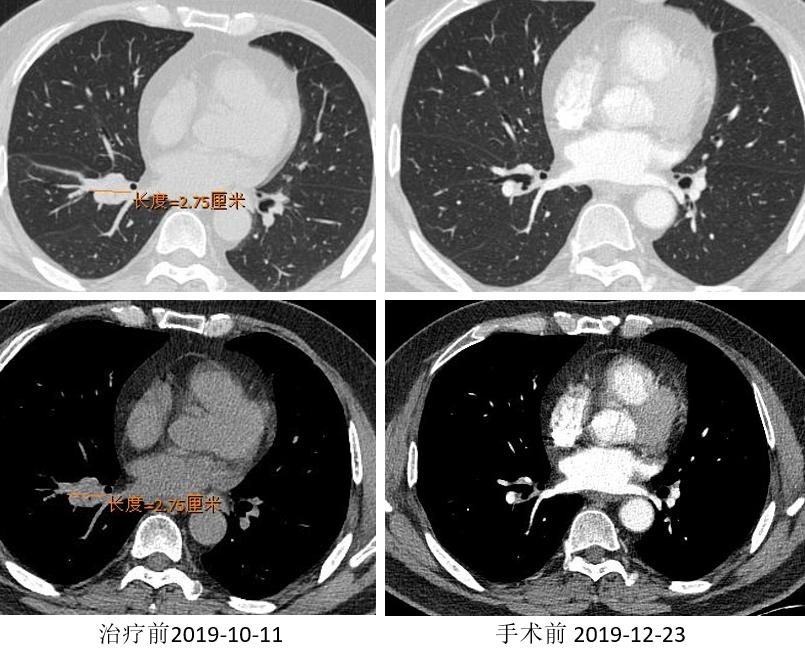

胸部CT

外周淋巴结CT

2019.12.17 行“VATS辅助右肺上叶切除术”。

术后冰冻病理:(右上叶)切片中见极少量异型细胞,恶性肿瘤可能。(第11组淋巴结)肺组织内见纤维组织增生伴炎细胞浸润及组织细胞反应。

疗效评价:MPR(病理显著缓解:接受治疗后肿瘤样本内的癌细胞占比<10%)。